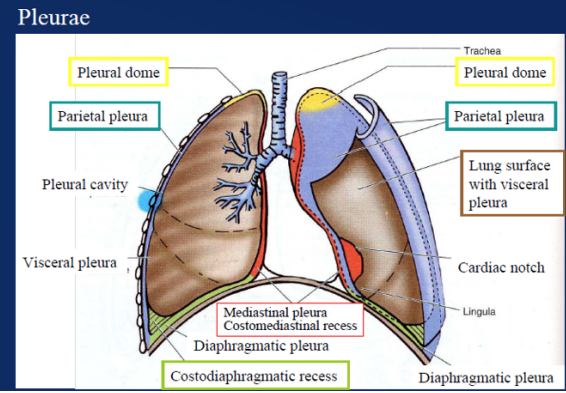

Pleural cavities

In the thorax we have 2 pleural cavities — each on either side of the mediastinum surrounding the lungs—

Superiorly — extend above rib I into the root of the neck

Inferiorly → Extend to a level just above the costal margin.

The medial wall of each pleural cavity is the mediastinum.

Each cavity is lined by a single layer of flat cells — the mesothelium — and an associated supporting connective tissue

Both layers form the actual “pleura”

Divided into 2 sections based on location —

Parietal pleura —

Outer section, associated with walls of the cavity

Visceral pleura —

Inner surface — adheres to and covers lungs

Pleural division based on location image

Parietal pleura —

Outer section, associated with walls of the cavity

Visceral pleura —

Inner surface — adheres to and covers lungs

Specificities about the parietal pleura

Pleura related to the ribs and intercostal spaces — called costal part

Pleura covering the diaphragm — diaphragmatic part

Pleura covering the mediastinum — mediastinal part

Pleura lining the cervical extension of the pleural cavity — cervical pleura

(dome of pleura or pleural cupola)

Pleural recesses

Two types of recesses —

The costodiaphragmatic recess

Also called costophrenic angles

Larger, located between the costal & diaphragmatic pleura of right & left pleural cavities

Occur at the costal reflection where the costal pleura becomes continuous with the diaphgramatic pleura

Deepest after broad expiration & shallowest after forced inspiration

The costomedisrinal recess

Smaller, anteriorly at the sternal reflection where the costal pleura is in contact with the mediastinal pleura

Larger on the left side due to cardiac notch of the left lung